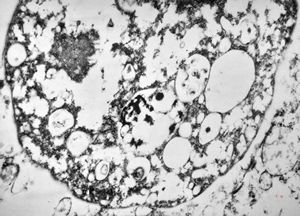

M,35y. | duodenum … lipid malabsorption - susp. hypo-beta-lipoproteinemia